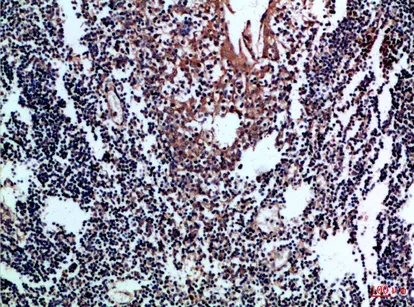

CD80 Rabbit Polyclonal Antibody

Cat: APRab08462